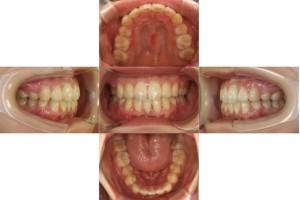

1年6カ月経過の口腔内の状態です。

全体のがたつきが改善されました。

※下顎左側7番目の歯ですが、患者様が治療期間を重視した為、同意のもと治療終了しています。

| 年齢層 | 20代 |

|---|---|

| 性別 | 女性 |

| 主訴 | 凸凹を治したい |

| 治療費用 | 1,397,000円 |

| 治療期間 | 1年6カ月 |

| 抜歯 | 上顎両側4番、下顎右側1番 |

| 矯正の装置 | リンガル(上下裏側装置) |

| 副作用、リスク | 歯肉退縮,歯根吸収,疼痛,咬合の違和感,装置の違和感,虫歯,歯肉炎 |